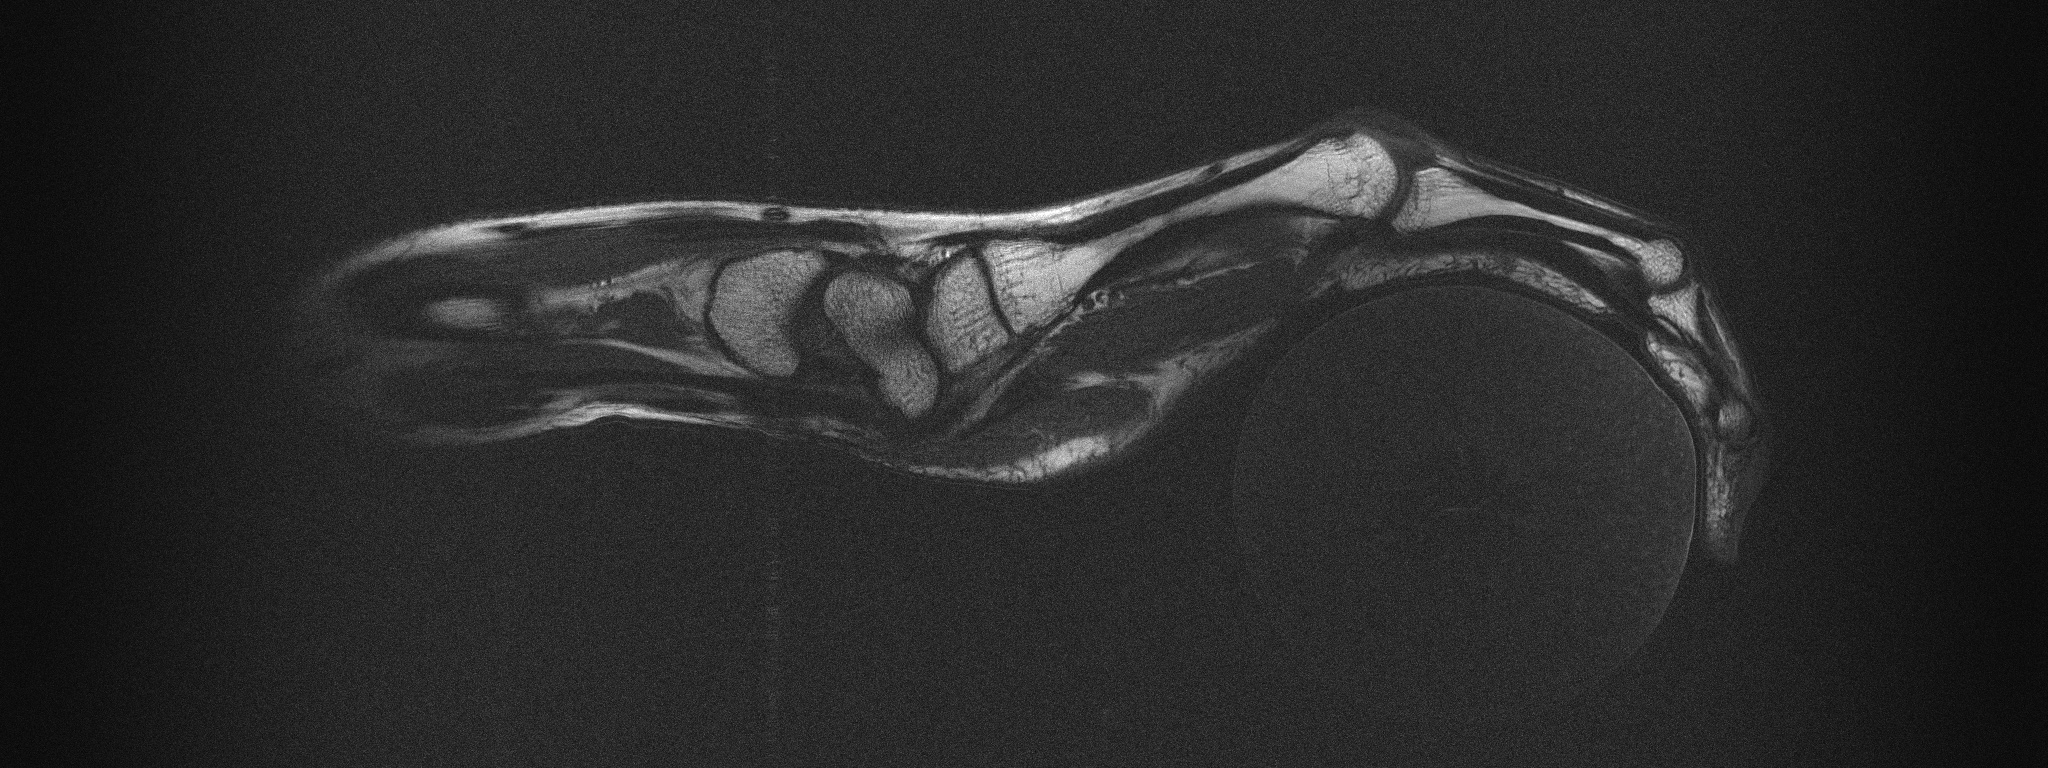

[Uncaptioned image]

Supplemental Figure 7: Sagittal T1 weighted image through the flexor tendon in the index finger while the hand is holding a peach. Sequence parameters: TR=400ms, TE=15ms, excitation angle = 90, refocusing angle = 180, Turbo factor 2, 2024x512 Matrix, 303.6x76.8mm FOV, 2mm slice thickness, 150x150 μ𝜇\mum resolution, total scan time = 1min 42s.